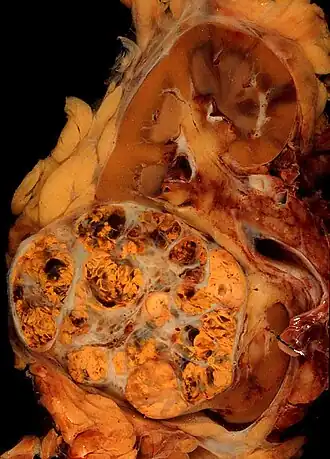

_Nephrectomy.jpg)

.jpg)

Ранее рак почки классифицировали по типу клеток и характеру роста. Позже было установлено что рак почки в абсолютном большинстве — смешанный. Современная классификация основывается на морфологических, цитогенетических и молекулярных исследованиях, а также иммуногистохимическом анализе и выделяет 5 видов почечно-клеточного рака[35]:

- светлоклеточный рак почки

- папиллярный (1 и 2 подтип) рак почки

- хромофобный рак почки

- онкоцитома почки

- рак собирательных трубочек

- медуллярный рак почки